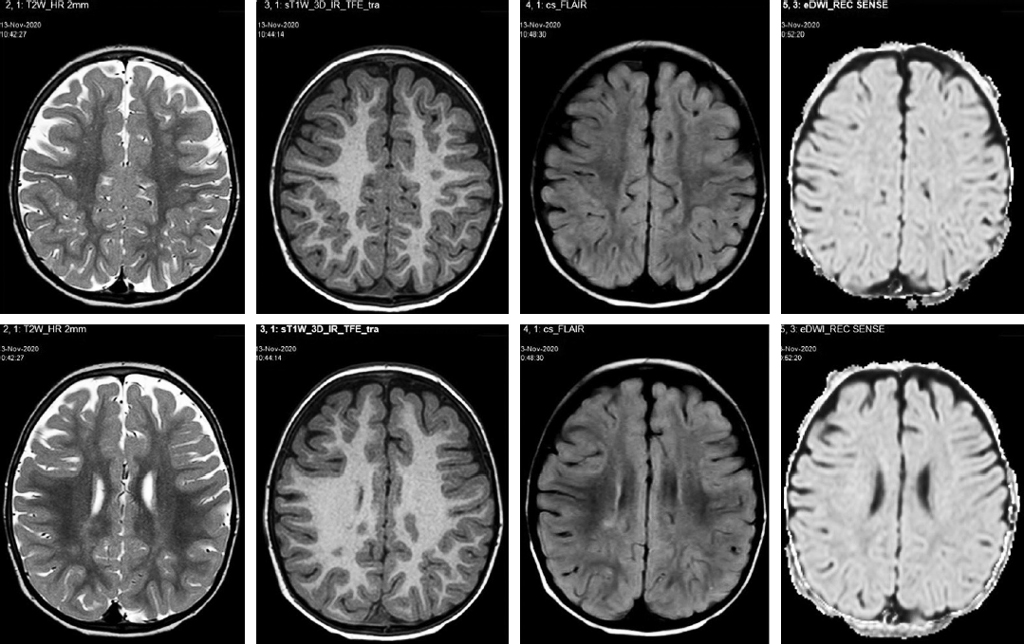

МРТ головного мозга 1,5 Тс: Умеренно выраженный перивентрикулярный глиоз (данные МРТ головного мозга представлены на рис. 1).

Рис. 1. МРТ головного мозга 1,5 Тс пациента (режимы T2W, T1W, FLAIR, DWI): умеренно выраженный перивентрикулярный глиоз